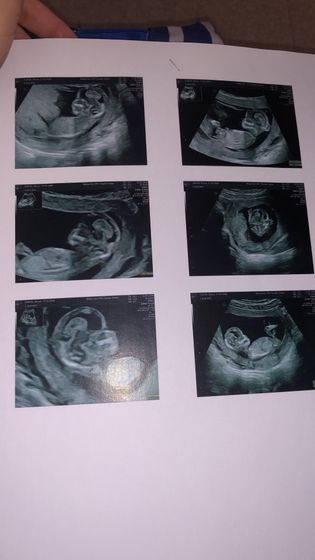

Была сегодня на первом Экографии, мой гинеколог который в 11 недель мне сказала что девочка,на простом Узи,не смогла посмотреть пол,Говорит не хочу ошибиться приди через месяц.я ей не верю,так как она была вся на нервах? кто разбирается в узи,есть тут что то?

Тут не разглядишь ещё. В 20 нед сходите повторно там уже точно скажут

У вас нет там снимка между ножек

Не видно